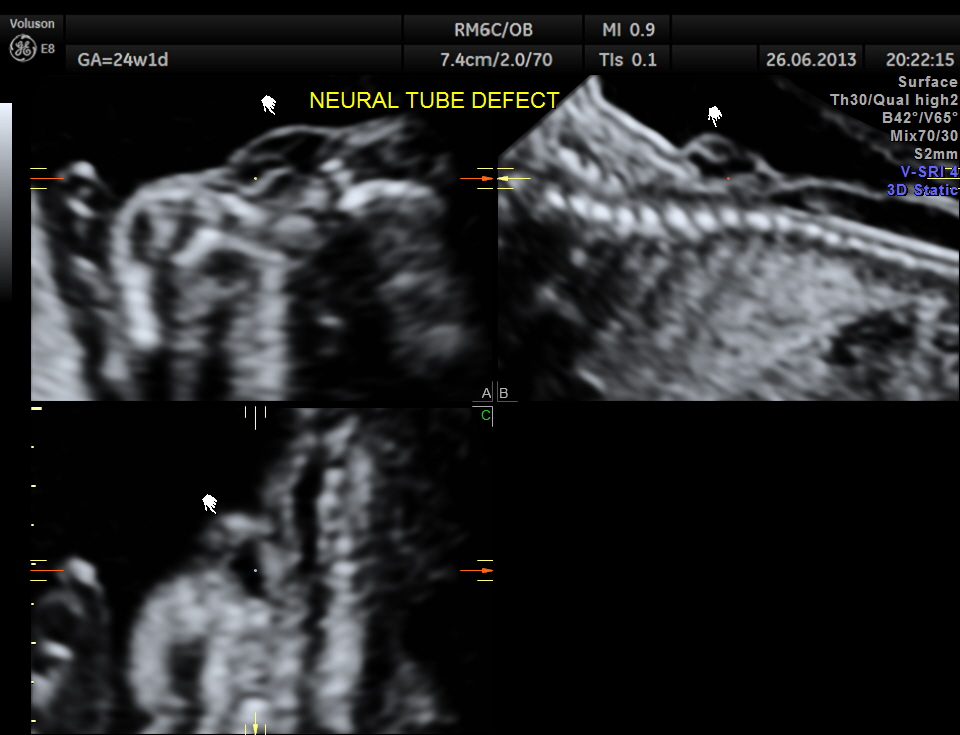

The spine was scanned next and the following images were seen

the next is a 3 d image of the open neural tube defect in the thoracic region

the following images are reconstructed images.